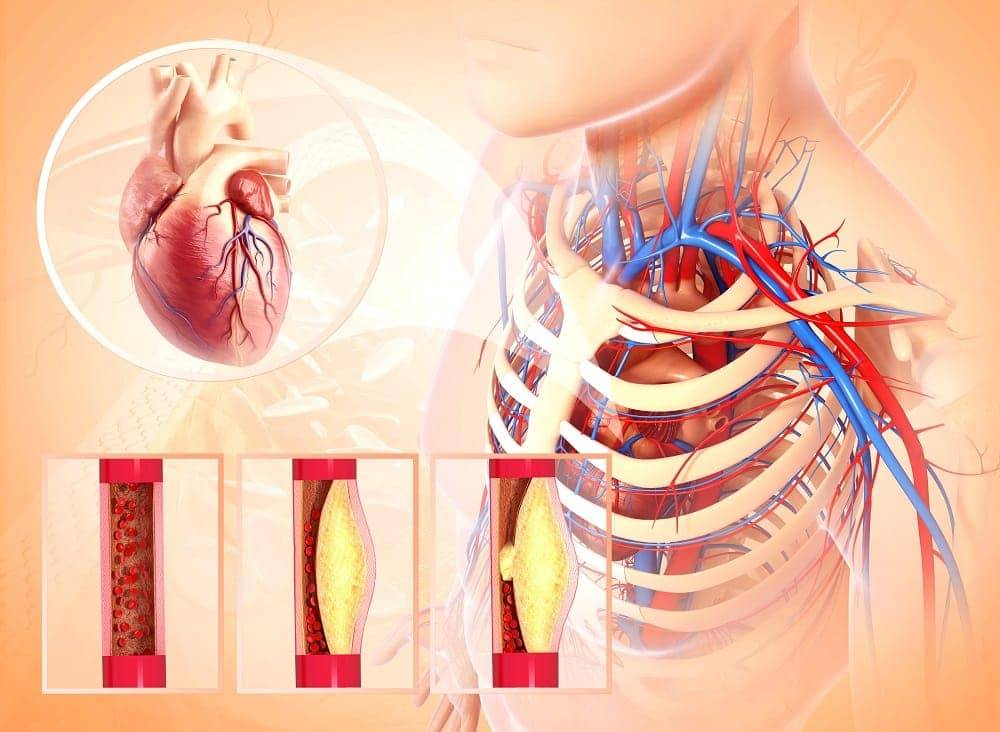

Хочу нашим телезрителям подробнее объяснить, что происходит. Смотрите, считается, что самый большой орган человека — это кожа. Но это не совсем так. На самом деле, сосудистая система — вот самый большой орган в нашем теле. И очевидно, что сбои в нем неизбежно приводят к проблемам в работе всего организма.

Только вдумайтесь: чтобы проехать расстояние, составляющее всю длину сосудов человека, на легковой машине со средней скоростью, Вам потребуется несколько лет. В вашем теле около 150 миллиардов капилляров. Если создать модель капилляров из спичек, она будет весить целых 8 Боингов! А если посчитать длину сосудов, то получится порядка 100 000 км.

Запомните: наше здоровье на 90% зависит от наших кровеносных сосудов.

Такая огромная система не может быть простой. Поэтому любые сбои в ее работе, даже незначительные, увы, неизбежно приводят к развитию самых разных патологических состояний.

Забитые сосуды приводят к нарушению в работе всех жизненно важных систем в организме.

Подобно отложениям в водопроводных трубах, на стенках сосудов годами откладывается холестерин и образовывает наслоения-бляшки, которые со временем сужают просвет и не дают крови проходить свободно.